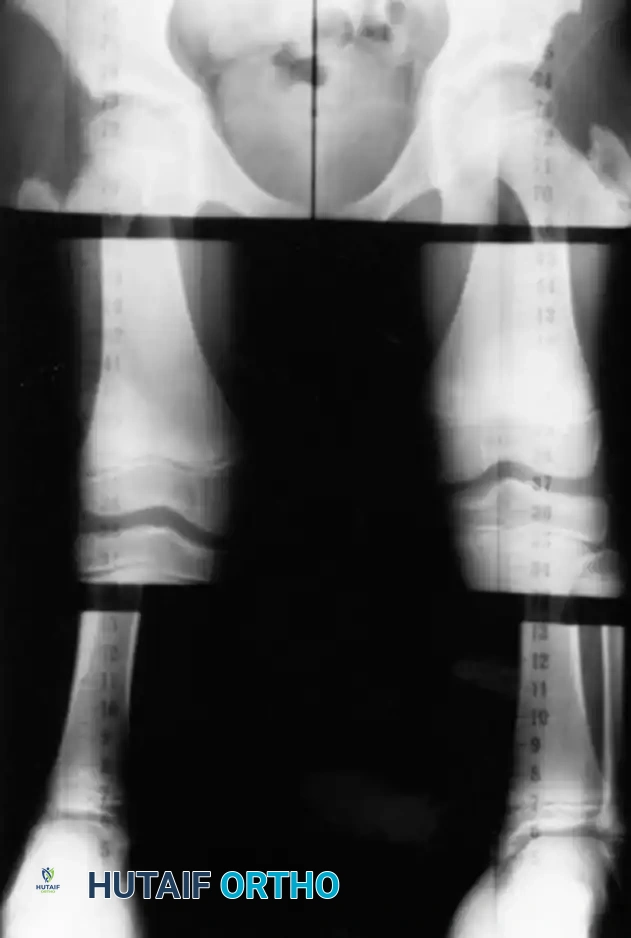

Radiographic measurements are paramount for surgical accuracy, as clinically palpable landmarks are subject to soft tissue interference. Two commonly used radiographic techniques are the standing orthoradiograph and the scanogram.

Both techniques involve placing a radiopaque ruler behind the patient's limbs.

* Orthoradiograph: Made on a single long cassette that includes the hip, knee, and ankle on a single exposure. A magnification marker placed on the leg at the level of the bone minimizes magnification error. Standing orthoradiographs offer the critical additional benefit of demonstrating overall mechanical limb alignment. It is imperative that the legs be positioned with the patellae facing strictly forward to avoid rotational artifact.

* Scanogram: Utilizes three separate, localized exposures of the hip, knee, and ankle joints. Because the x-ray beam is centered directly over each joint, parallax error is virtually eliminated. However, it requires the child to remain absolutely still for all three exposures.